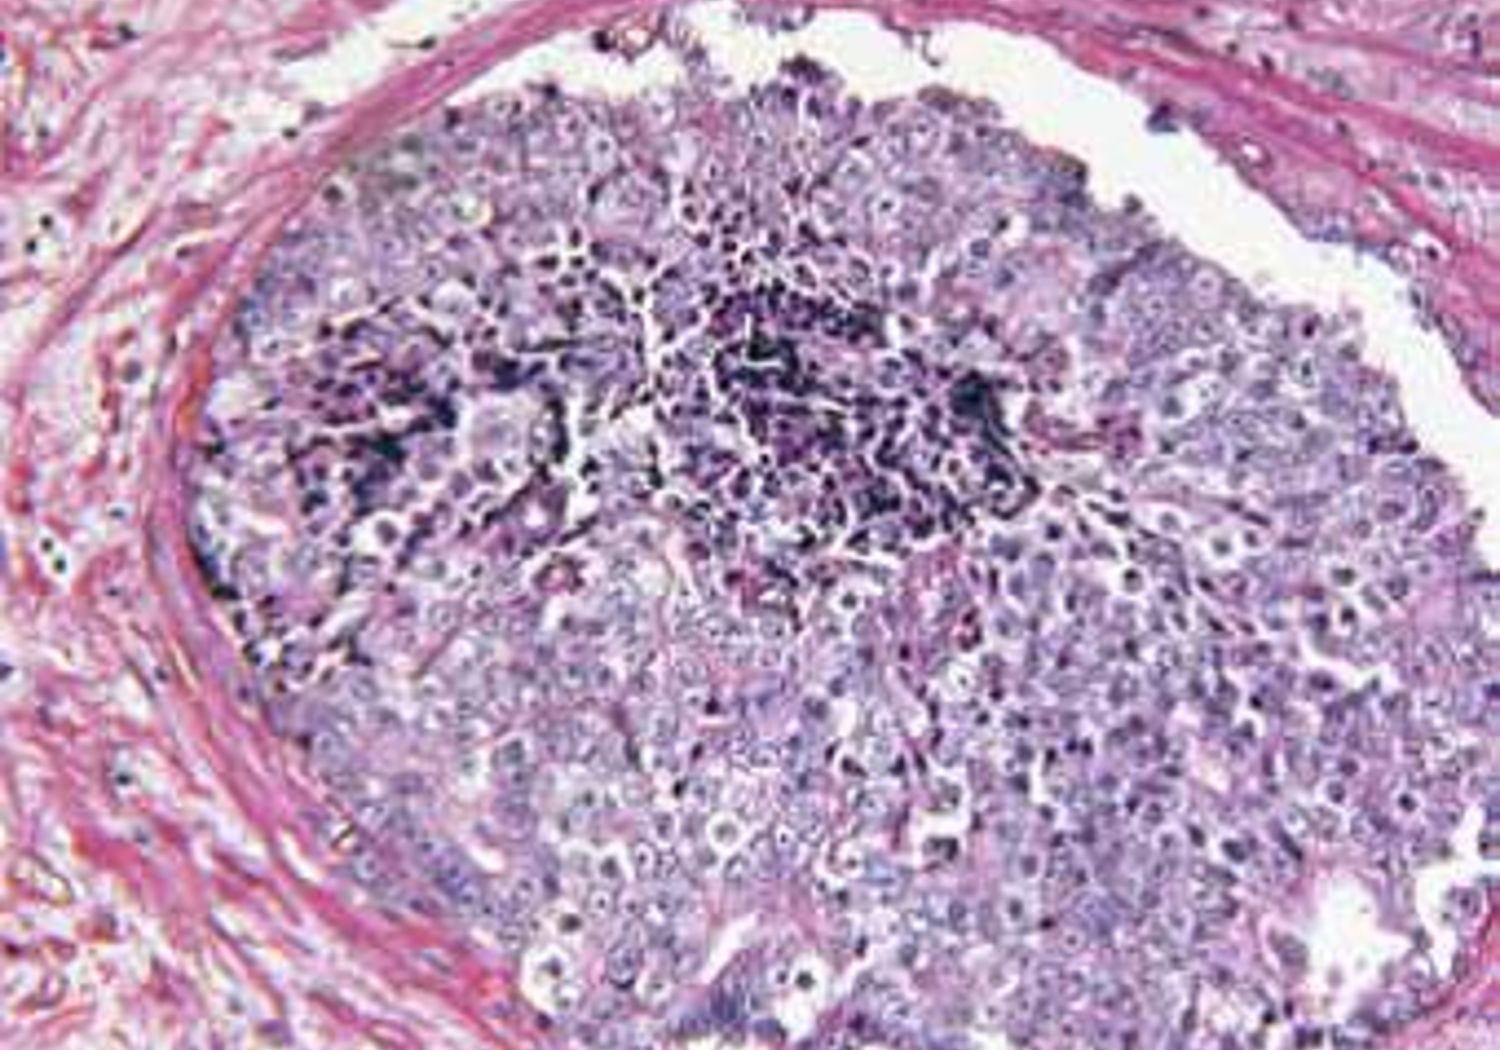

Prostate Gland Adenocarcinoma